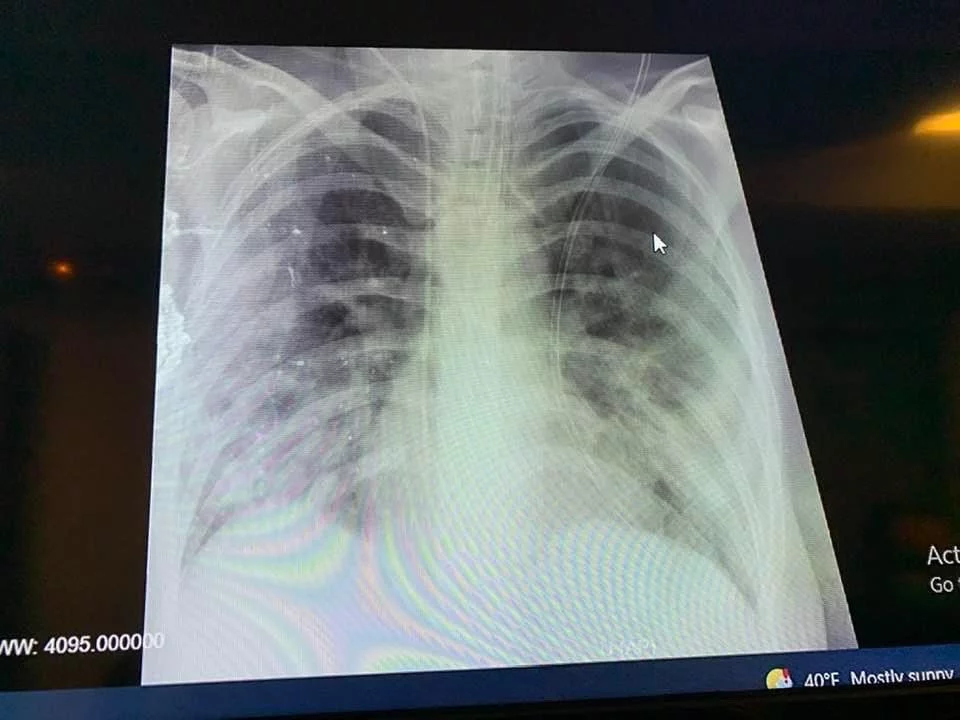

Η ακτινογραφία της 41χρονης ανεμβολίαστης εγκύου

Σοκαριστική είναι η ακτινογραφία πνεύμονα της 41 ετών εγκύου που δημοσιοποίησε στο Facebook ο Καθηγητης Παιδιατρικής του ΑΠΘ, Κοσμάς Σαραφίδης.

«Ακτινογραφία θώρακα ανεμβολίαστης εγκύου που διασωληνώθηκε χτες και γέννησε πολύ πρόωρα λόγω της βαρύτητας της κατάστασης της. Μόνο ο μισός από τον κάθε πνεύμονα της λειτουργεί», έγραψε αρχικά στην ανάρτηση του και συνέχισε: «Άγνωστη η πρόγνωση της μητέρας. Και ένα νεογνό που θα μπορούσε να γεννηθεί στην ώρα του, τελειόμηνο, και να αποφύγει όλους τους κινδύνους της προωρότητας. Αυτό που γράφεται σε ανάλογες περιπτώσεις, ότι δηλαδή το μωρό σώθηκε, είναι τελείως ανακριβές. Μήνες εντατικής νοσηλείας για να επιβιώσει και μόνο! Και με νευροεξέλιξη απρόβλεπτη σε μεγάλο βαθμό! ΚΡΙΜΑ, ΚΡΙΜΑ!Τα σχόλια είναι περιττά!».